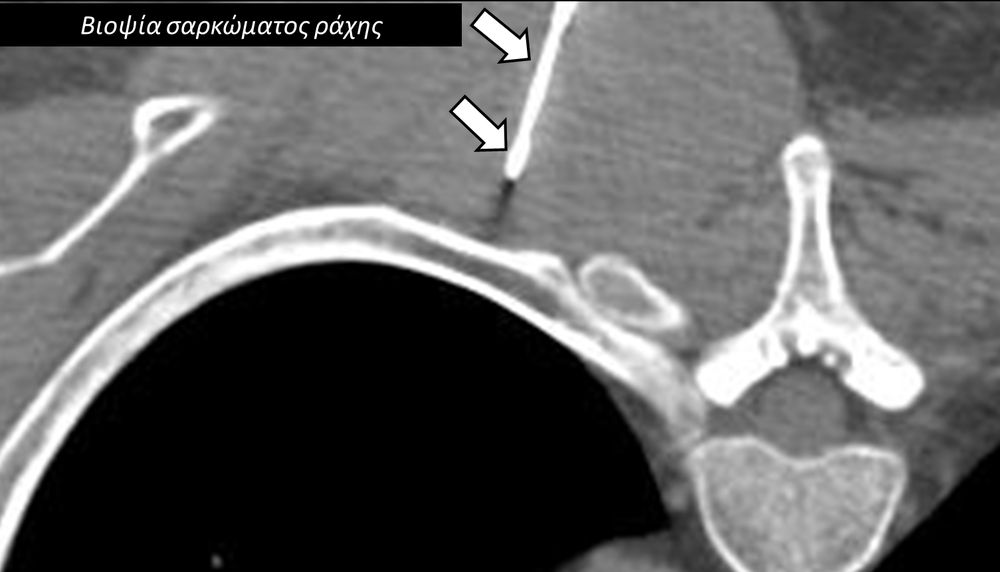

Η διαδερμική βιοψία είναι μία ελάχιστα επεμβατική μέθοδος λήψης υλικού από τον όγκο για κυτταρολογική και ιστολογική εξέταση, από εστιακές αλλοιώσεις του ήπατος, πνεύμονα, νεφρού κλπ. Συστήνεται από τον κλινικό ιατρό ανάλογα με το είδος και το μέγεθος της βλάβης και πραγματοποιείται με ασφάλεια από επεμβατικό ακτινολόγο με την καθοδήγηση αξονικού τομογράφου ή υπερήχων. Στη σύγχρονη ογκολογική θεραπεία όπου γίνεται προσπάθεια καταπολέμησης του καρκίνου σε μοριακό επίπεδο κρίνεται αναγκαία η ακριβής ιστολογική ταυτοποίηση του όγκου ώστε να εφαρμοσθεί εξατομικευμένη θεραπεία για το βέλτιστο αποτέλεσμα. Οι κατευθυνόμενες βιοψίες στοχευουν στο να παρέχουν στον κλινικό ογκολόγο το απαραίτο ιστοπαθολογικό υλικό που θα του επιτρέψει να εφαρμόσει την κατάλληλη θεραπεία για τον ογκολογικό ασθενή.